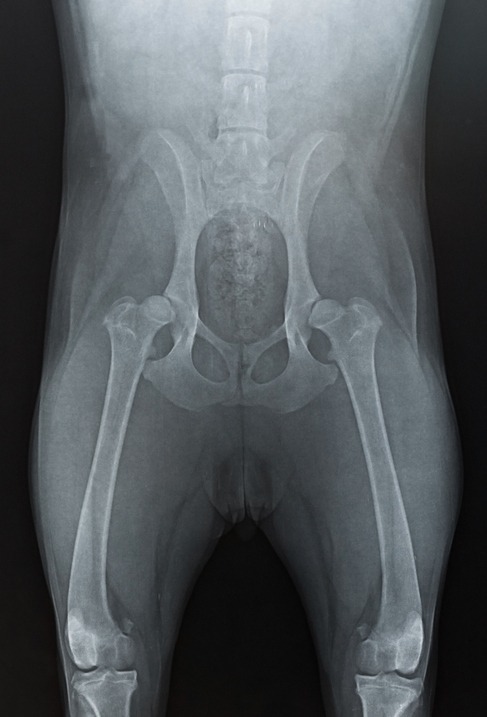

Bei Verdacht einer Hüftgelenksdysplasie sollten Sie einen auf HD-Röntgen spezialisierten Tierarzt aufsuchen. Er überstreckt die Hinterläufe und vermisst die Fehlstellung im Röntgen. Eine lockere Hüfte ist bei dieser Methode in den meisten Fällen zu erkennen, jedoch nicht in allen. Besser ist ein PennHIP-Röntgen. Mittels der PennHIP-Methode kann mithilfe von drei unterschiedlichen Röntgenaufnahmen eine frühzeitige und umfassende Beurteilung erreicht werden. Eine vorliegende Hüftgelenksdysplasie (HD) wird in Schweregrade eingeteilt und muss im weiteren Verlauf immer wieder kontrolliert werden.